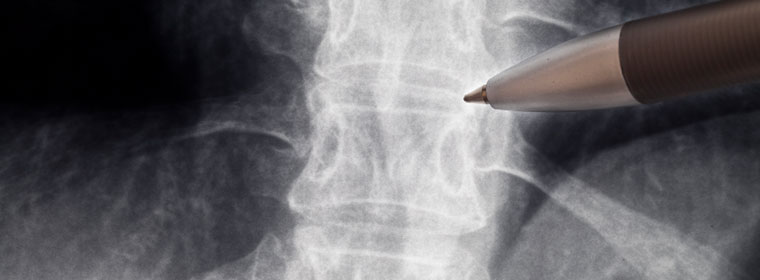

Most commonly, fluoroscopic x-ray images are used to guide placement of the epidural steroid injection needle to the proper location in the epidural space, that space within the spinal canal but outside of the dural tube. The dura is a thick membrane within which are the spinal cord, the spinal nerves and the spinal fluid. The steroids should be injected outside the dura but within the spinal canal.